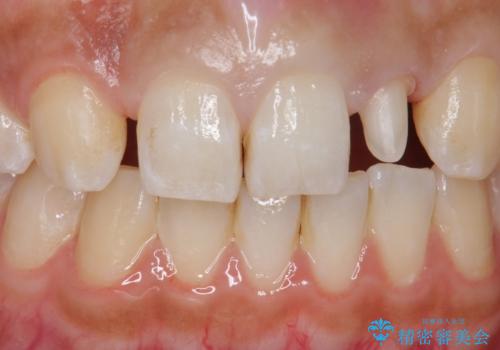

変色した前歯をキレイにしたい ジルコニアクラウンでの修復

- 左上の前歯の変色が気になるとのことで来院されました。

もともと小さい歯(矮小歯)に樹脂が盛り足されている状態でした。

今後の変色をなくすために樹脂ではなくセラミックでの治療を行います。

セラミックでの治療をすることにより今後の変色を抑えることができます。

色・形ともに改善することができ大変喜んでいただけました。